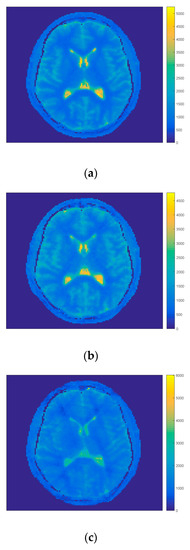

Figure A1.

T1 maps of volunteer 1 calculated by the FIR-MAP-MFM after (a) 50, (b) 150, (c) 300, (d) 450, (e) 600 and (f) 750 numbers of iterations.